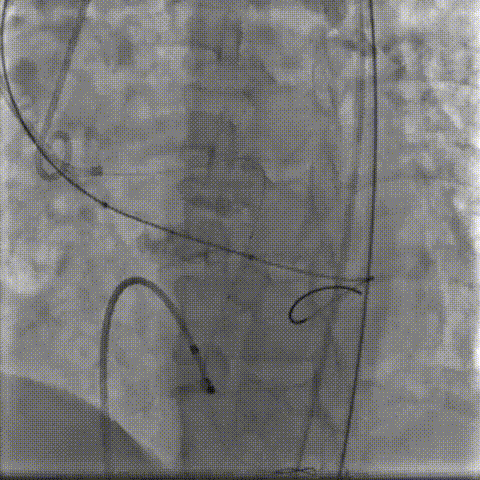

术中影像:

双侧侧髂血管造影血管纤细

LCA保护下18mm球囊预扩,扩张充分,瓣叶向LCA开口偏移;输送器过弓顺利。

瓣环下精准定位稳定释放,瓣膜工作位造影考虑瓣叶推挤LCA阻挡临界状态,释放“烟囱支架”。

瓣膜稳定脱钩,20mm球囊后扩,“烟囱支架”Kissing,后扩后支架形态改善。

左髂动脉“翻山“,造影+覆膜支架预备伴随保护下顺利退鞘,造影观察无血管损伤,手术顺利结束。